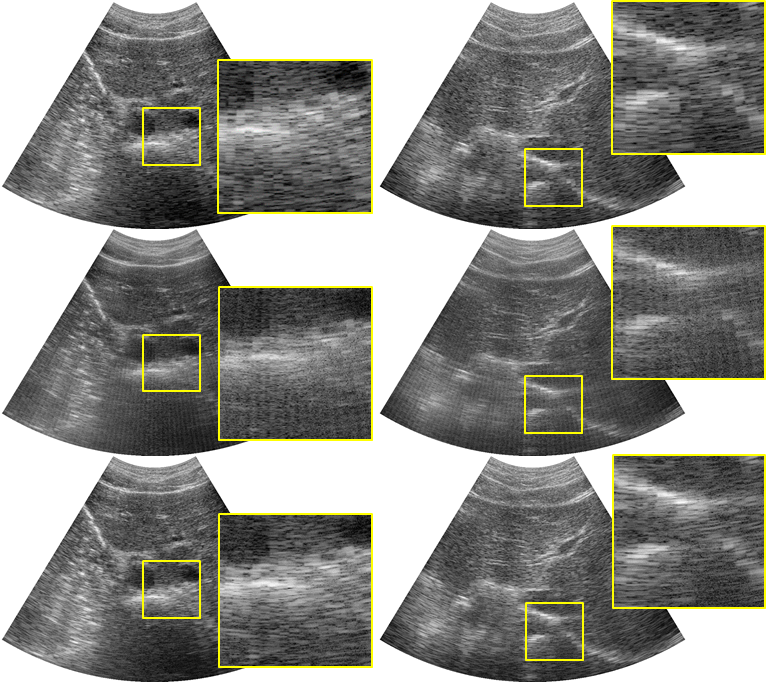

Next, we use the network trained using the RF data from linear array transducer to interpolate the missing RF data from a convex array probe. The reconstruction results from a DAS beamformer are shown in in Fig.5. Because the Rx-SC data of linear array transducer and convex array transducer are similar, the DAS beamformer provided very accurate reconstruction results without any line artifacts or blurring from CNN-based RF interpolation. It is also remarkable that the accurate reconstruction was obtained for the liver region, which was never seen by the network trained using the linear array transducer data. The results confirmed the universality of the algorithm.